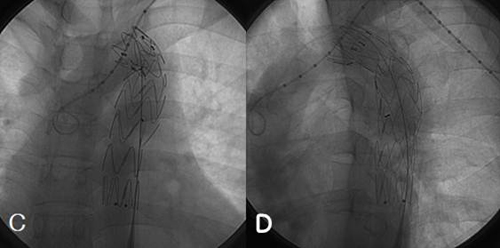

Sudden disruption of the aortic isthmus (A).Successful repair of a blunt aortic injury can be accomplished using endolumi- COVER STORY The Gore TAG thoracic device should not be oversized more than 18% based on the aortic diameter, as indicated by the ... Get Doc